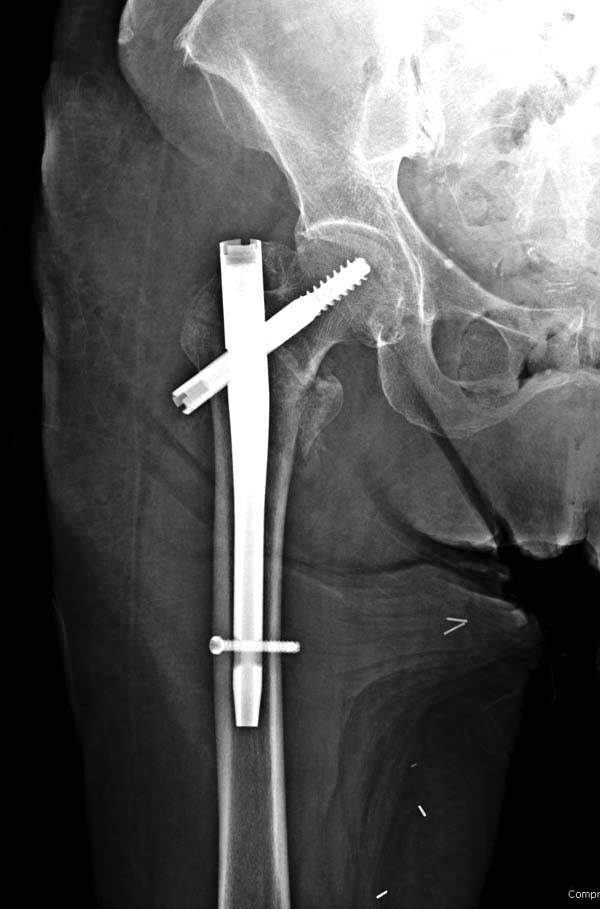

Первые снимки показывают технические погрешности установки DHS. Не была достигнута репозиция, конечность в флексии и шейка в ротации. Сегодня все меньше обращают внимание на параметры для оценки репозиции (S контуры Lowell в обеих проекциях и Garden Alignment Index, в норме 155 и 180 градусов), хотя такие простые тесты помогли бы дорепонировать смещение. Винт находится сзади в головке, что при нагрузке поменяет вектор и вместо компрессии в линии перелома срежет головку-Cut Out!

В зависимости от дистанции линии перелома и латерального кортекса надо использовать разной длины barrel, т.е. конец баррели не должен доходить до пределов перелома. Здесь конец длинного ствола упирается в медиальный фрагмент, что мешает созданию компрессии, а более короткий barrel создал бы запас для компрессии. В боковой пластине вместо 4х можно было ограничится двумя шурупами, потому что головка шурупа в 4.5 мм выдерживает давление до 350 кг.